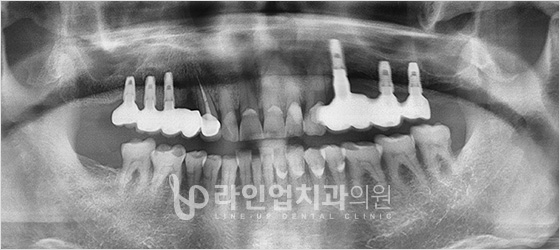

种植牙 치료 사례

치료전 Before

치료후 After

上臼齿种植牙